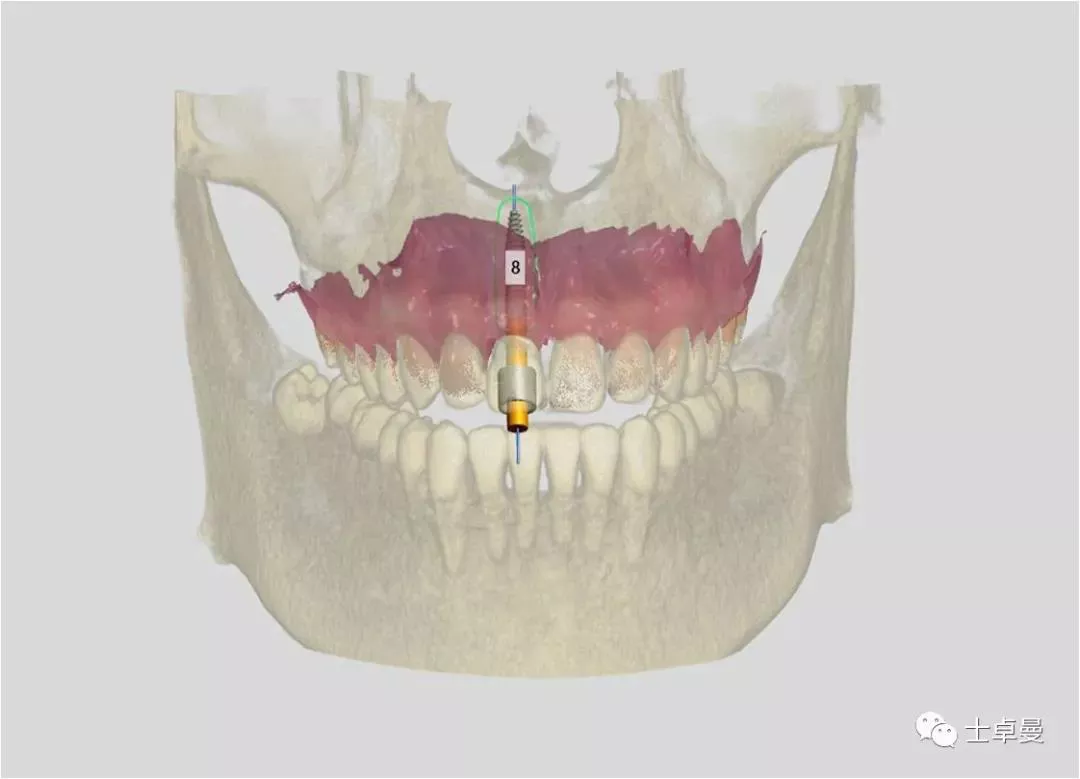

· 术前口扫,设计种植修复方案并以修复为导向制作种植外科导板;

· 部分拔除11残根,保留唇侧牙盾片;

· 在外科导板辅助下即刻植入Straumann® Roxolid® SLActive® BLT种植体;

· 条件允许时进行即刻修复。

· Straumann® Roxolid® SLActive® BLT 4.1mm×16mm种植体;

术前设计规划

治疗计划

· 应用盾技术进行11即刻种植即刻修复。